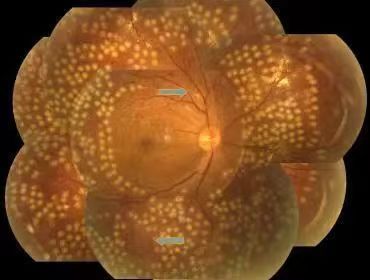

全视网膜激光光凝术后